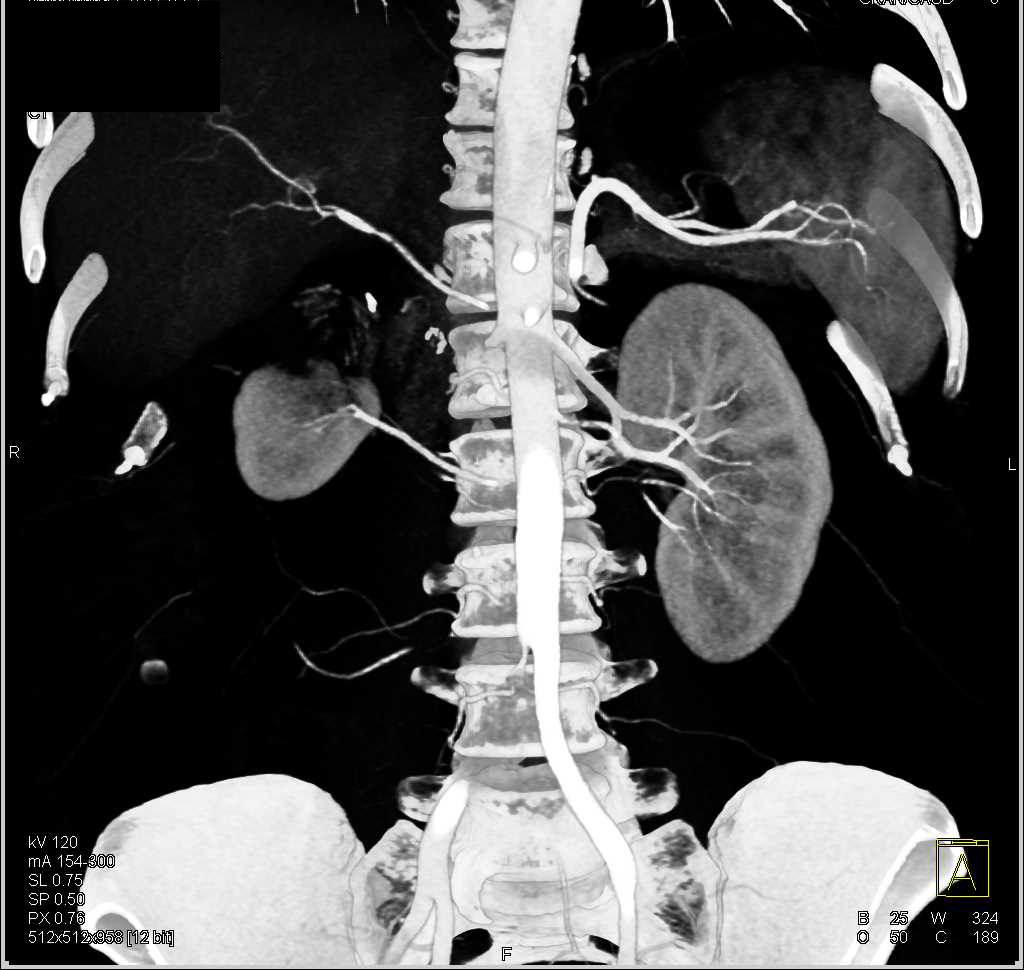

Transitional Cell Carcinoma Left Renal Pelvis and Extends in the Ureter